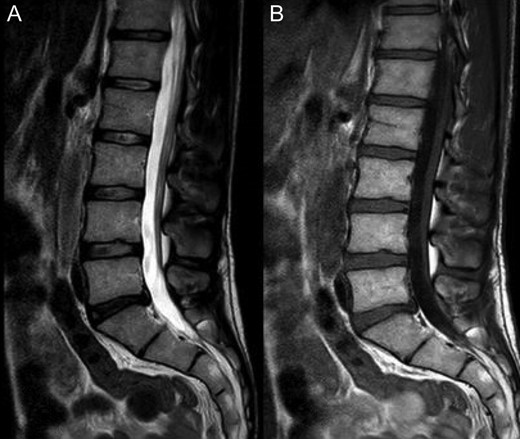

Lumbar magnetic resonance imaging‘(MRI) revealed L5-S1 disc protrusion and no abnormality on joints. A small interspinous bursitis is described on L3-L4 and L5-S1 spinous processes (Fig. 3). An L4-S1 CT: did not reveal classic imaging characteristics for Baastrup’s disease.

A: T2, B: T1; Weighted sagittal Lumbar MRI showing discal hernia L5-S1, small interspinous bursitis L3-L4 and L4-L5, L5-S1 rift + edema, spina bifida occulta (usually asymptomatic).